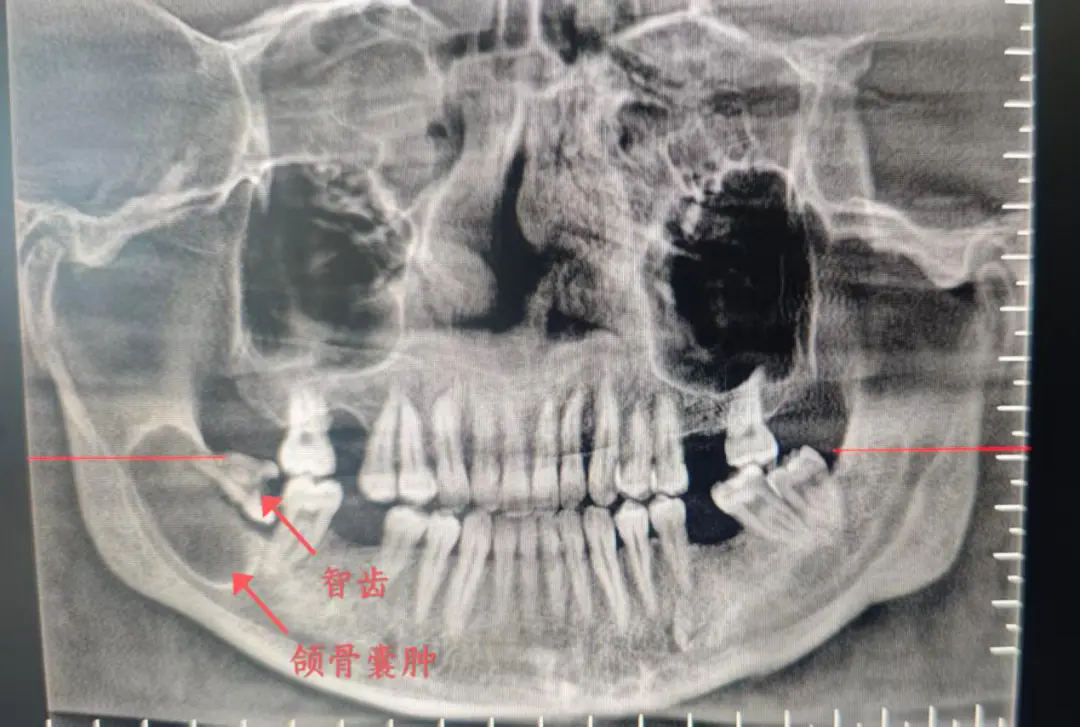

该患者因“右侧面部下颌区间断性麻木”就诊,孔琳杰医生结合临床经验,建议其进行口腔颌面部CBCT检查,最终明确诊断为下颌第三磨牙(智齿)引发的“右侧下颌骨囊肿”,囊肿破坏颌骨范围长轴最大径约3cm。颌骨囊肿虽为良性病变,但持续增大可能导致面部畸形、牙齿松动甚至病理性骨折,面部麻木正是神经受压的重要警示,需及时手术干预。

横着长的智齿(近中水平阻生)像一颗"***",持续刺激颌骨,诱发牙源性颌骨囊肿,如同腐坏的牛肉会污染整块好肉

1.拍片发现智齿横长(全景片即可诊断)